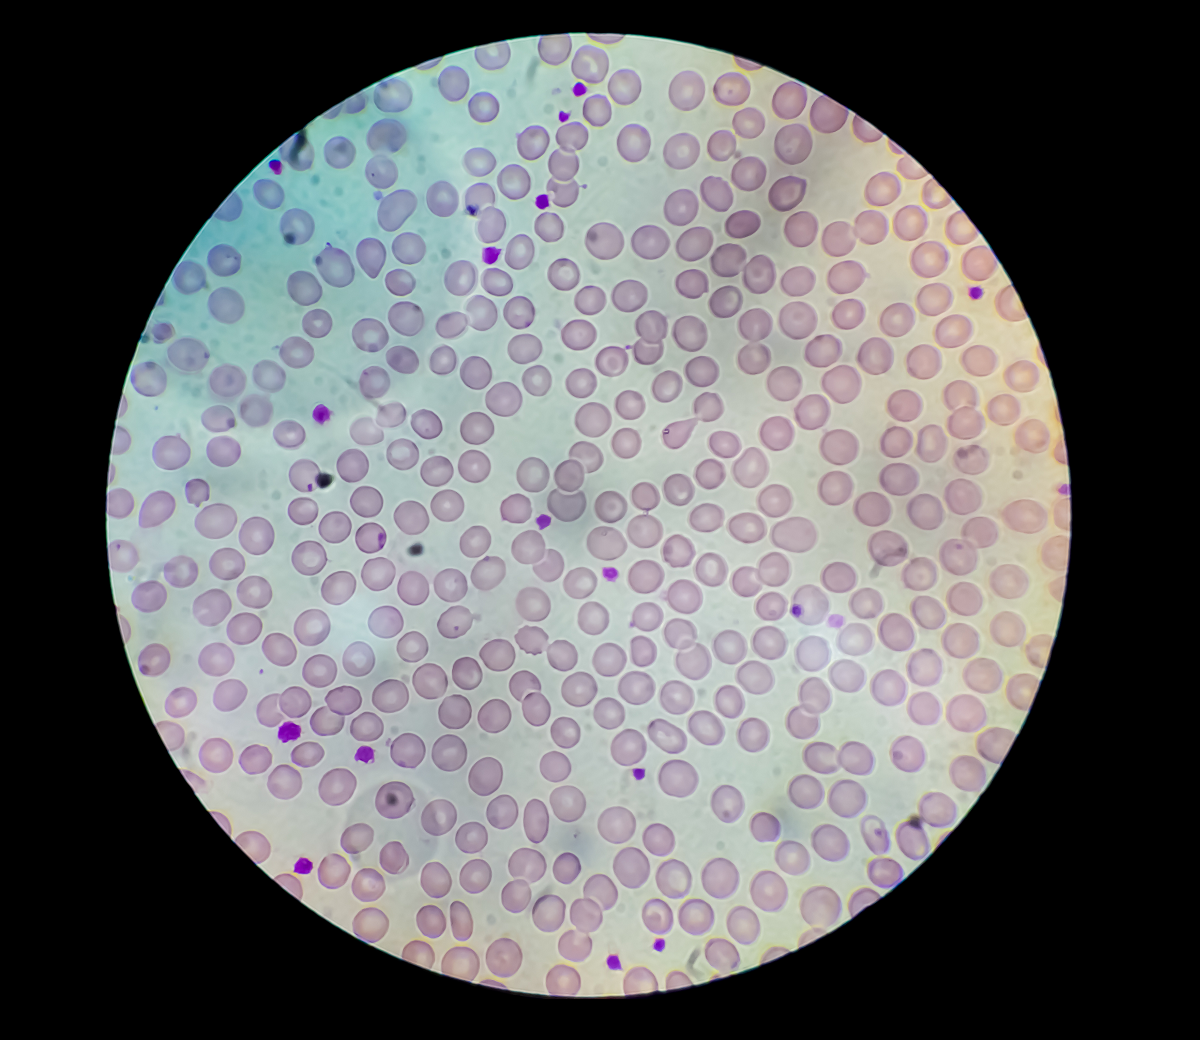

Карнификация Легкого: Микропрепараты и Диагностика

Раздел: Калейдоскоп образов